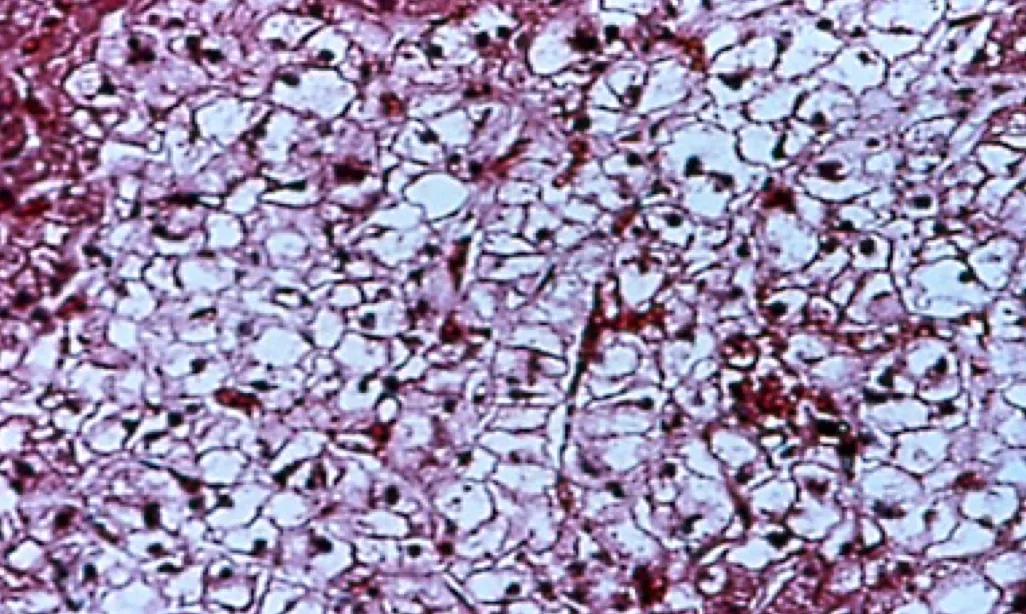

The liver of a dog with cirrhosis due to chronic hepatotoxicity from phenobarbital is shown in Figure 2. Typical findings include increased total ALP usually less than 5 times upper limit of normal, with ALT usually less than 2 times upper limit of normal. GGT, AST, total serum bile acids should be within the normal range.11,12 Ultrasonography yields normal findings, and most dogs do not have hepatomegaly. Biopsy shows diffuse cytoplasmic granularity due to proliferation of smooth endoplasmic reticulum.

Cirrhotic liver in a dog secondary to chronic hepatotoxicity from phenobarbital